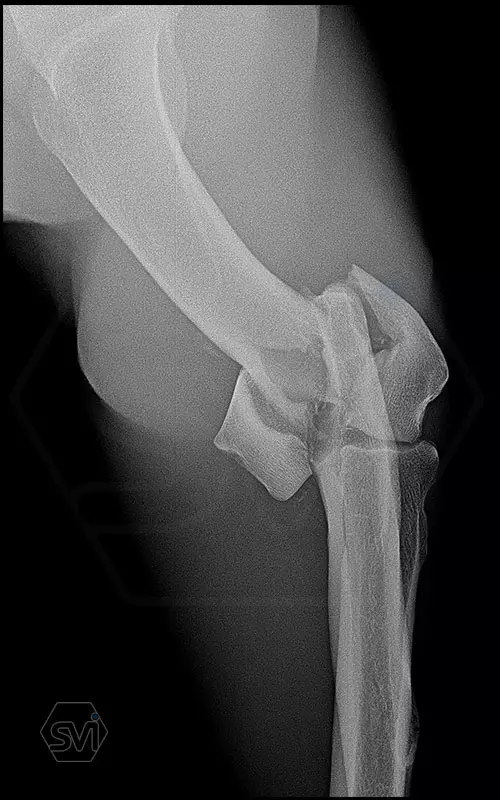

Nightmare for all of us: diastal humeral Y-fracture in a large active dog (German Shepherd)